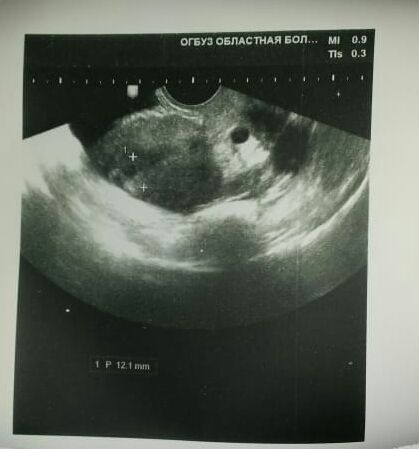

Сегодня получила результаты УЗИ. Одно радует, сказали что кист нет. Завтра прием у врача. Но я все никак не дождусь его. Опять умудрилась себя "намотать".